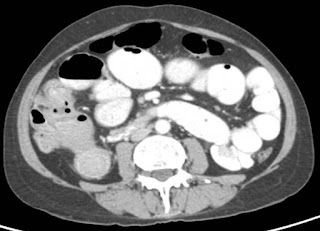

An elderly woman in her 5th decade presented with acute intestinal obstruction. Her contrast enhanced abdominal computed tomography (CT) scan showed mass lesion in cecum – ascending colon (Figure 1).

Figure 1. Carcinoma right colon with acute_Intestinal obstruction

She underwent right hemicolectomy with primary anastomosis and had an uneventful recovery. The biopsy was suggestive of adenocarcinoma T3N1. She was stared on adjuvant chemotherapy after 3 weeks and is currently well 4 years after surgery.